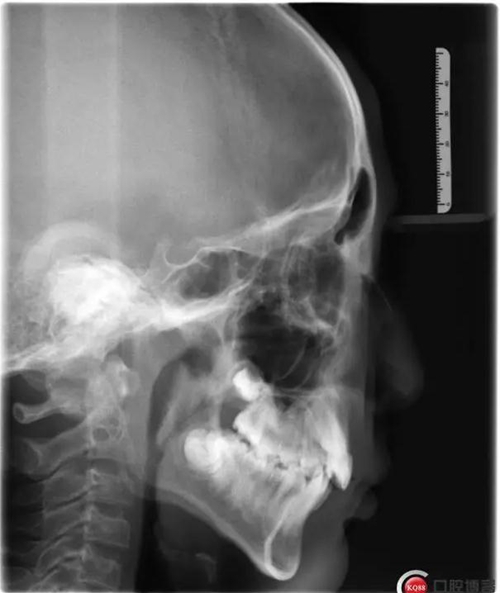

1500865770_445373.jpg1500865976_358577.jpg

此病例主要考慮的是擁擠度,磨牙及尖牙關(guān)系,前牙覆合覆蓋,生長潛力和智齒。